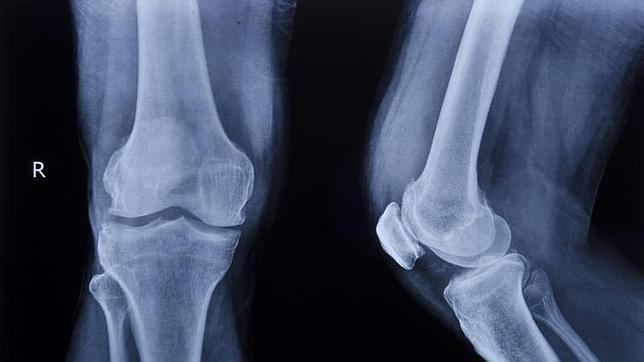

Doctores pertenecientes al Hospital Xijing han conseguido implantar en tres pacientes prótesis de titanio que reproducían huesos gracias a la impresión en 3D, tal y como han dado a conocer hoy medios oficiales.

En las intervenciones se extrajeron huesos afectados por tumores cancerígenos (en concreto ... un omóplato, una clavícula y una pelvis) y se sustituyeron por las prótesis impresas. Guo Zheng, experto en ortopedia y encargado de dirigir las intervenciones, explicó que las operaciones lograron resolver un problema, el de la sustitución de huesos afectados por tumores, que no es fácil de resolver mediante prótesis convencionales, que con frecuencia no se adaptan a este tipo de pacientes. Según las mismas fuentes, los pacientes se están recuperando satisfactoriamente de las cirugías dos meses después de las intervenciones.